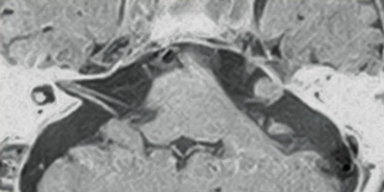

3D-BASG

VASC-ASL is a non-contrast MRA imaging function that uses 3D BASG (Balanced SARGE) to visualize the blood flow labelled with IR pulses. This function is used to produce images of portal veins, renal arteries, and upper and lower extremity arteries.